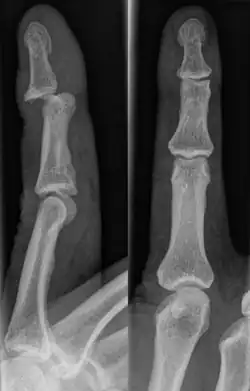

Fractures

Fractures are instances where the bone's structural integrity has been compromised.[20] If a jammed finger produces a fracture, pain will be greatest at the bone as opposed to the joint.[2] There may also be visual deformation of the bone itself.[6] As with any skeletal injury, an x-ray can be conducted to verify the presence of a fracture.[1] The distal phalanx is especially vulnerable to avulsion fractures.[1] These avulsion fractures are common following a first time dislocation of the DIP.[1]

Injuries that force the finger towards the back of the hand may cause damage to the volar plate.[12] This is a ligament on the palm side of the hand that prevents hyperextension.[13] Volar plate damage may be assessed by pressing the finger bones from the back towards the palm. If either individual bone of the affected joint moves freely towards the palm, it is indicative of a tear.[2] Tears of the volar plate may lead to an avulsion fracture – when a piece of bone is pulled off with the ligament.[13] This is due to the thickness and strength of the ligament.[14] To rule out an avulsion fracture, x-rays are frequently utilized in evaluation of suspected volar plate tears.[12] Volar plate avulsions are most evident on lateral views.[2]

DIP dislocations may also involve a complete tear of the extensor digitorum tendon.[16] This tendon is part of a muscle that straightens the tip of the finger.[9] If left untreated, this may lead to permanent inability to straighten the finger at the affected DIP joint.[16] This particular type of injury is known as mallet finger. It too, is commonly associated with an avulsion fracture.[17] It is a variation of a jammed finger, where the extensor tendons on the back of the finger are damaged.[18] Mallet finger occurs in similar situations as a jammed finger. The tendon that extends the tip of the finger is torn due to trauma causing it to flex beyond normal range.[17] It is characterized by a difficulty extending the finger or opening the hand.[19] Symptoms common to jammed fingers are likely, though a painless mallet finger is not uncommon.[2]